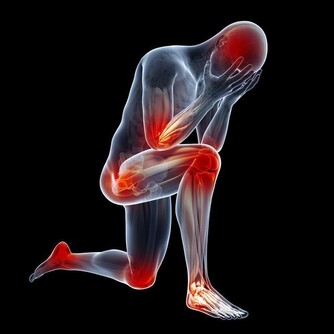

6、水腫

飲水太多,或者是睡眠時間過長、過於肥胖等,

眼瞼、臉部、小腿等部位可以出現稍微的水腫,假如不是這樣,就要懷疑是不是腎臟有了題目。